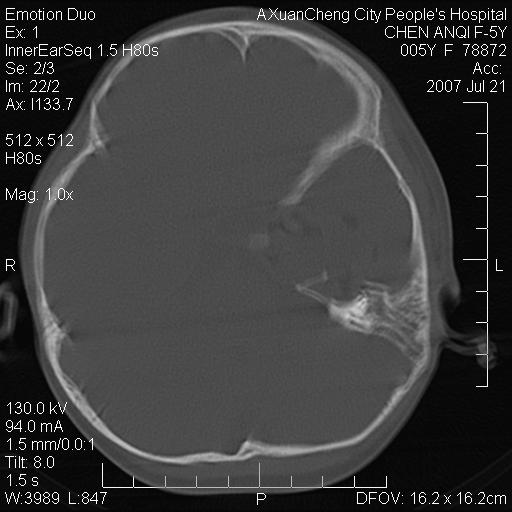

标题: PED0273:5岁,左耳流脓痛疼一周,颅底骨质破坏 [打印本页]

标题: PED0273:5岁,左耳流脓痛疼一周,颅底骨质破坏

患儿5岁,左耳流脓痛疼一周,左外耳道肉芽组织填塞 软组织窗显示病灶内结节状低密度影为气体密度

左侧中耳炎并胆脂瘤,左颞骨岩部骨质破坏并颅内感染积气。

考虑化脓性中耳乳突炎伴胆脂肪瘤形成并左颞叶感染,不除外合并嗜酸性肉芽肿.